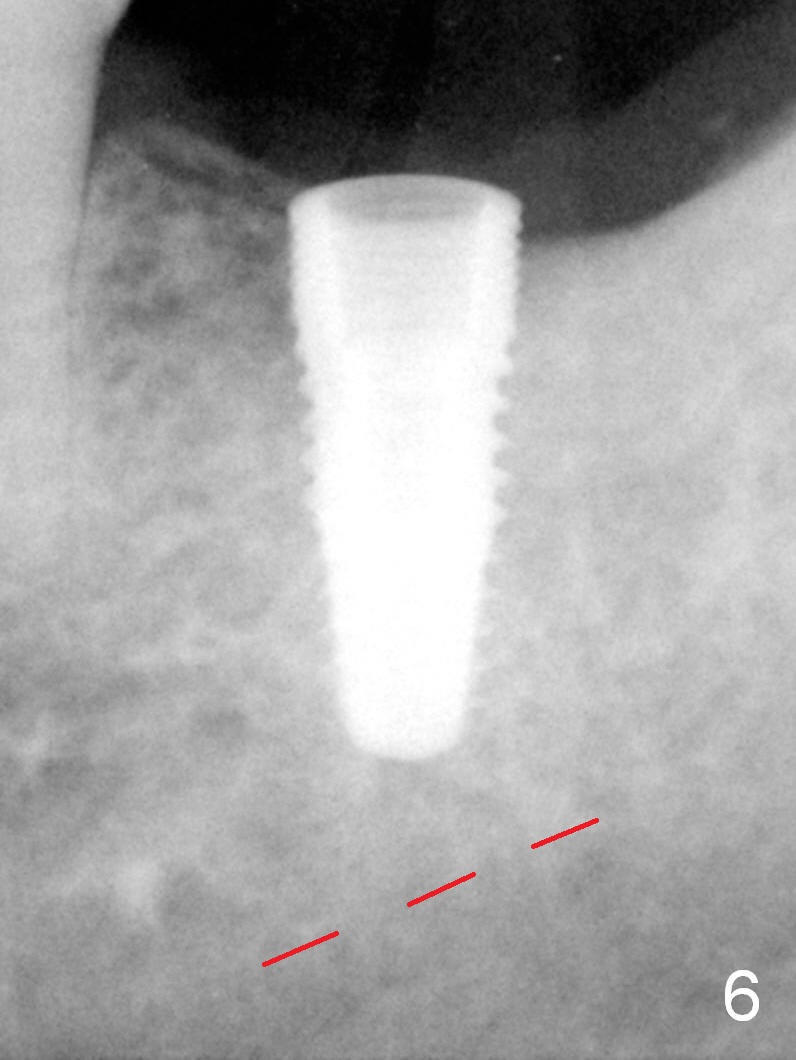

A 48-year-old lady is a dental phobic, requesting extraction of the lower left 2nd molar (Fig.1).   She returns for implant placement 9 months post extraction (Fig.2).  The ridge is mildly to moderately atrophic.  It appears that a 5x12 mm implant is appropriate for the site (Fig.3).  For safety, osteotomy is initiated at the depth of 10 mm; it appears that there is enough height for a 12 mm implant (Fig.4).  The depth is controlled by drill stopper (Fig.5 S).  Finally a 5x12 mm implant is apparently safely placed (Fig.6).  A healing abutment is placed and the incision is sutured with 4-0 Chromic gut (Fig.7).  Perio dressing is applied around the healing abutment for wound protection (Fig.8).  It appears that the healing abutment (Fig.8': *) helps stabilize the perio dressing, which remains in place 1 week postop.  When the perio dressing is removed, the wound around the healing abutment is healing (Fig.9).  There is no bone loss around the implant 3 months postop (Fig.10 (H: healing abutment), or 16 months postop (i.e., 9 months post cementation, Fig.11,12).  The patient complains of pain when she chews with the implant crown, but pain stops whenever she does not bite.  Percussion does not elicit any discomfort.  The gingiva is healthy.  There is possibility of the buccal plate being thin or the lingual plate being perforated in the submandibular fossa.  If the discomfort remains the same next 6 months, CBCT will be prescribed.